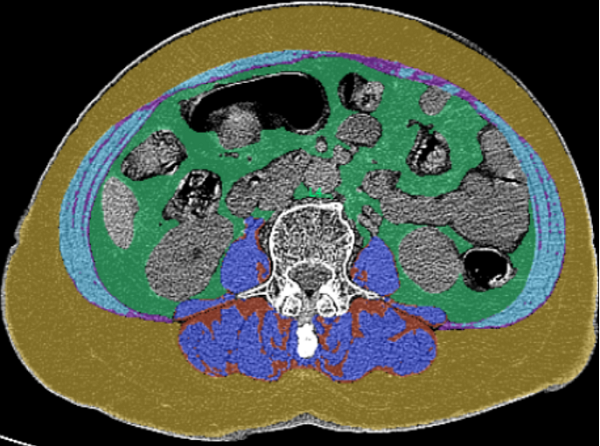

CT腹部内脏脂肪测量作为目前评估体脂分布的先进影像学方法之一,能够分别量化腹部皮下脂肪面积和腹腔内脏脂肪的总体积与面积,从而客观反映脂肪在人体内的实际分布情况。

现代医学影像中,基于临床已有的腹部CT平扫图像,可借助专业后处理软件及QCT技术,在不增加额外扫描和辐射暴露的前提下,对内脏脂肪进行同步、定量分析。该方法为肥胖相关代谢异常的评估与健康管理提供了重要的影像学参考。